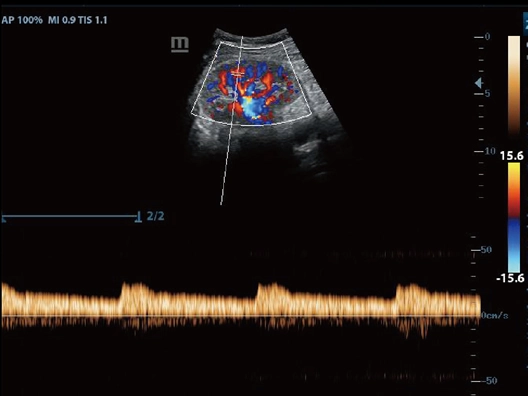

Клинические изображения

- Режимы сканирования: B/M/Color Dopler/Color M/Power/Directional Power Doppler Flow Imaging

- PW Doppler, включая HPRF (High Pulsed Repitition Frequency)